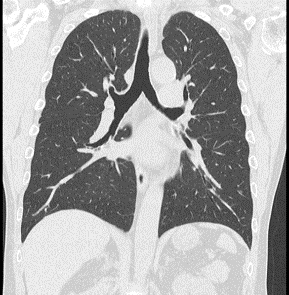

■80列のマルチスライスCTで全身を短時間で撮影することができます。肺の検査で2~3秒、肺~骨盤までの検査でも8秒程で撮影可能です。

■AI(Deep Learning:深層学習)を用いた画像再構成技術を用いて、被ばく線量を減らしながら高画質な画像を得ることができます。